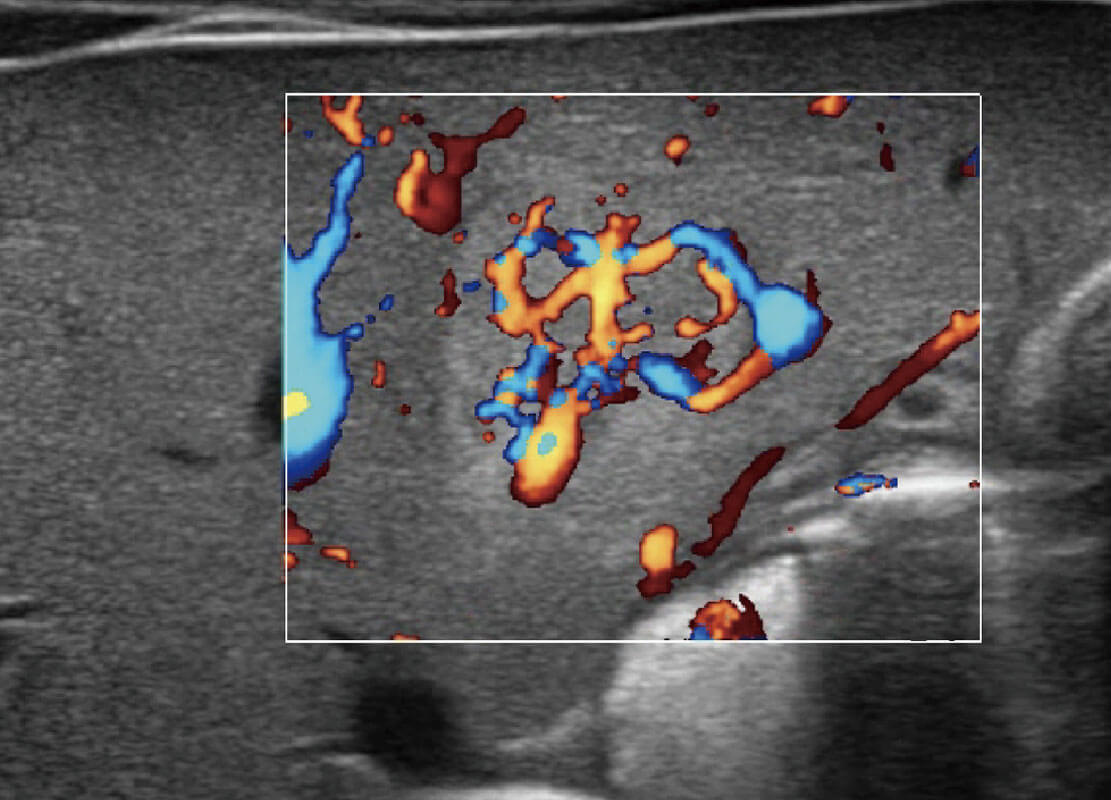

乳腺超声 / 新生儿

P60搭载宽频带线阵探头、宽景成像、弹性成像技术,为您提供乳腺应用方案。P60支持高频相控阵探头、线阵探头、腹部高频探头、腹部微凸探头等,丰富的探头群搭载敏感的彩色血流成像,适用于新生儿多种脏器检测要求,满足新生儿筛查需求。

• 乳腺癌显微血流

• 新生儿肝血管癌